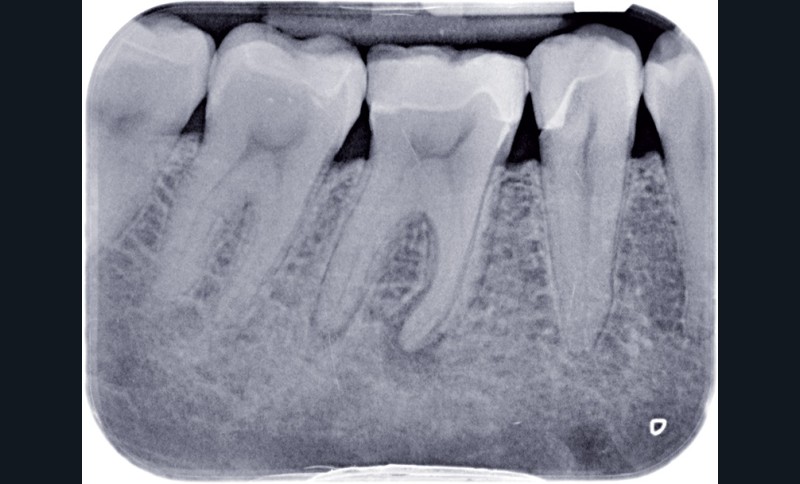

La dentisterie contemporaine privilégie les modes de restauration conservateurs avec pour objectif de préserver la vitalité pulpaire. Cependant, des échecs peuvent survenir du fait de nouvelles agressions et ce, malgré la qualité des procédures opératoires mises en œuvre (fig. 1).

Dans ces situations, le praticien est conduit à dépulper et à restaurer les dents traitées endodontiquement. Les traitements doivent alors s’inscrire dans le concept du continuum endo-restaurateur qui a été défini comme étant « le processus spatio-temporel sans interruption ni rupture qui débute par l’accès à l’endodonte et s’achève avec la mise en place de la restauration prothétique d’usage » (1). Il existe bien une continuité, du traitement endodontique à la restauration fonctionnelle d’usage qui conditionne le pronostic et les résultats du traitement à long terme (fig. 2).